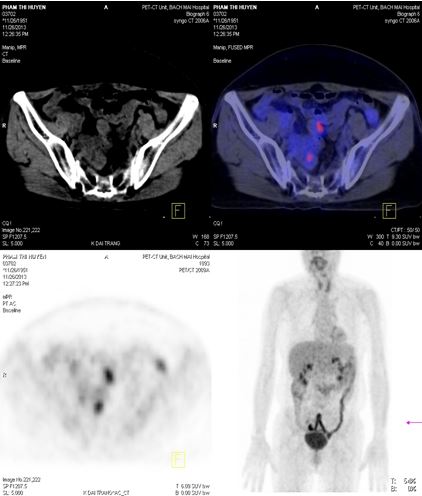

Chụp PET /CT đánh giá sau điều trị :

+ Không thấy hình ảnh tăng hấp thu và chuyển hoá FDG bất thường tại các vị trí trong cơ thể.

Hình 5. Hình chụp PET/CT: Khối tổn thương tại tuyến thượng thận phải đã tan biến

Hình 6. Hình chụp PET/CT: Khối tổn thương phúc mạc tại hố chậu phải đã tan biến